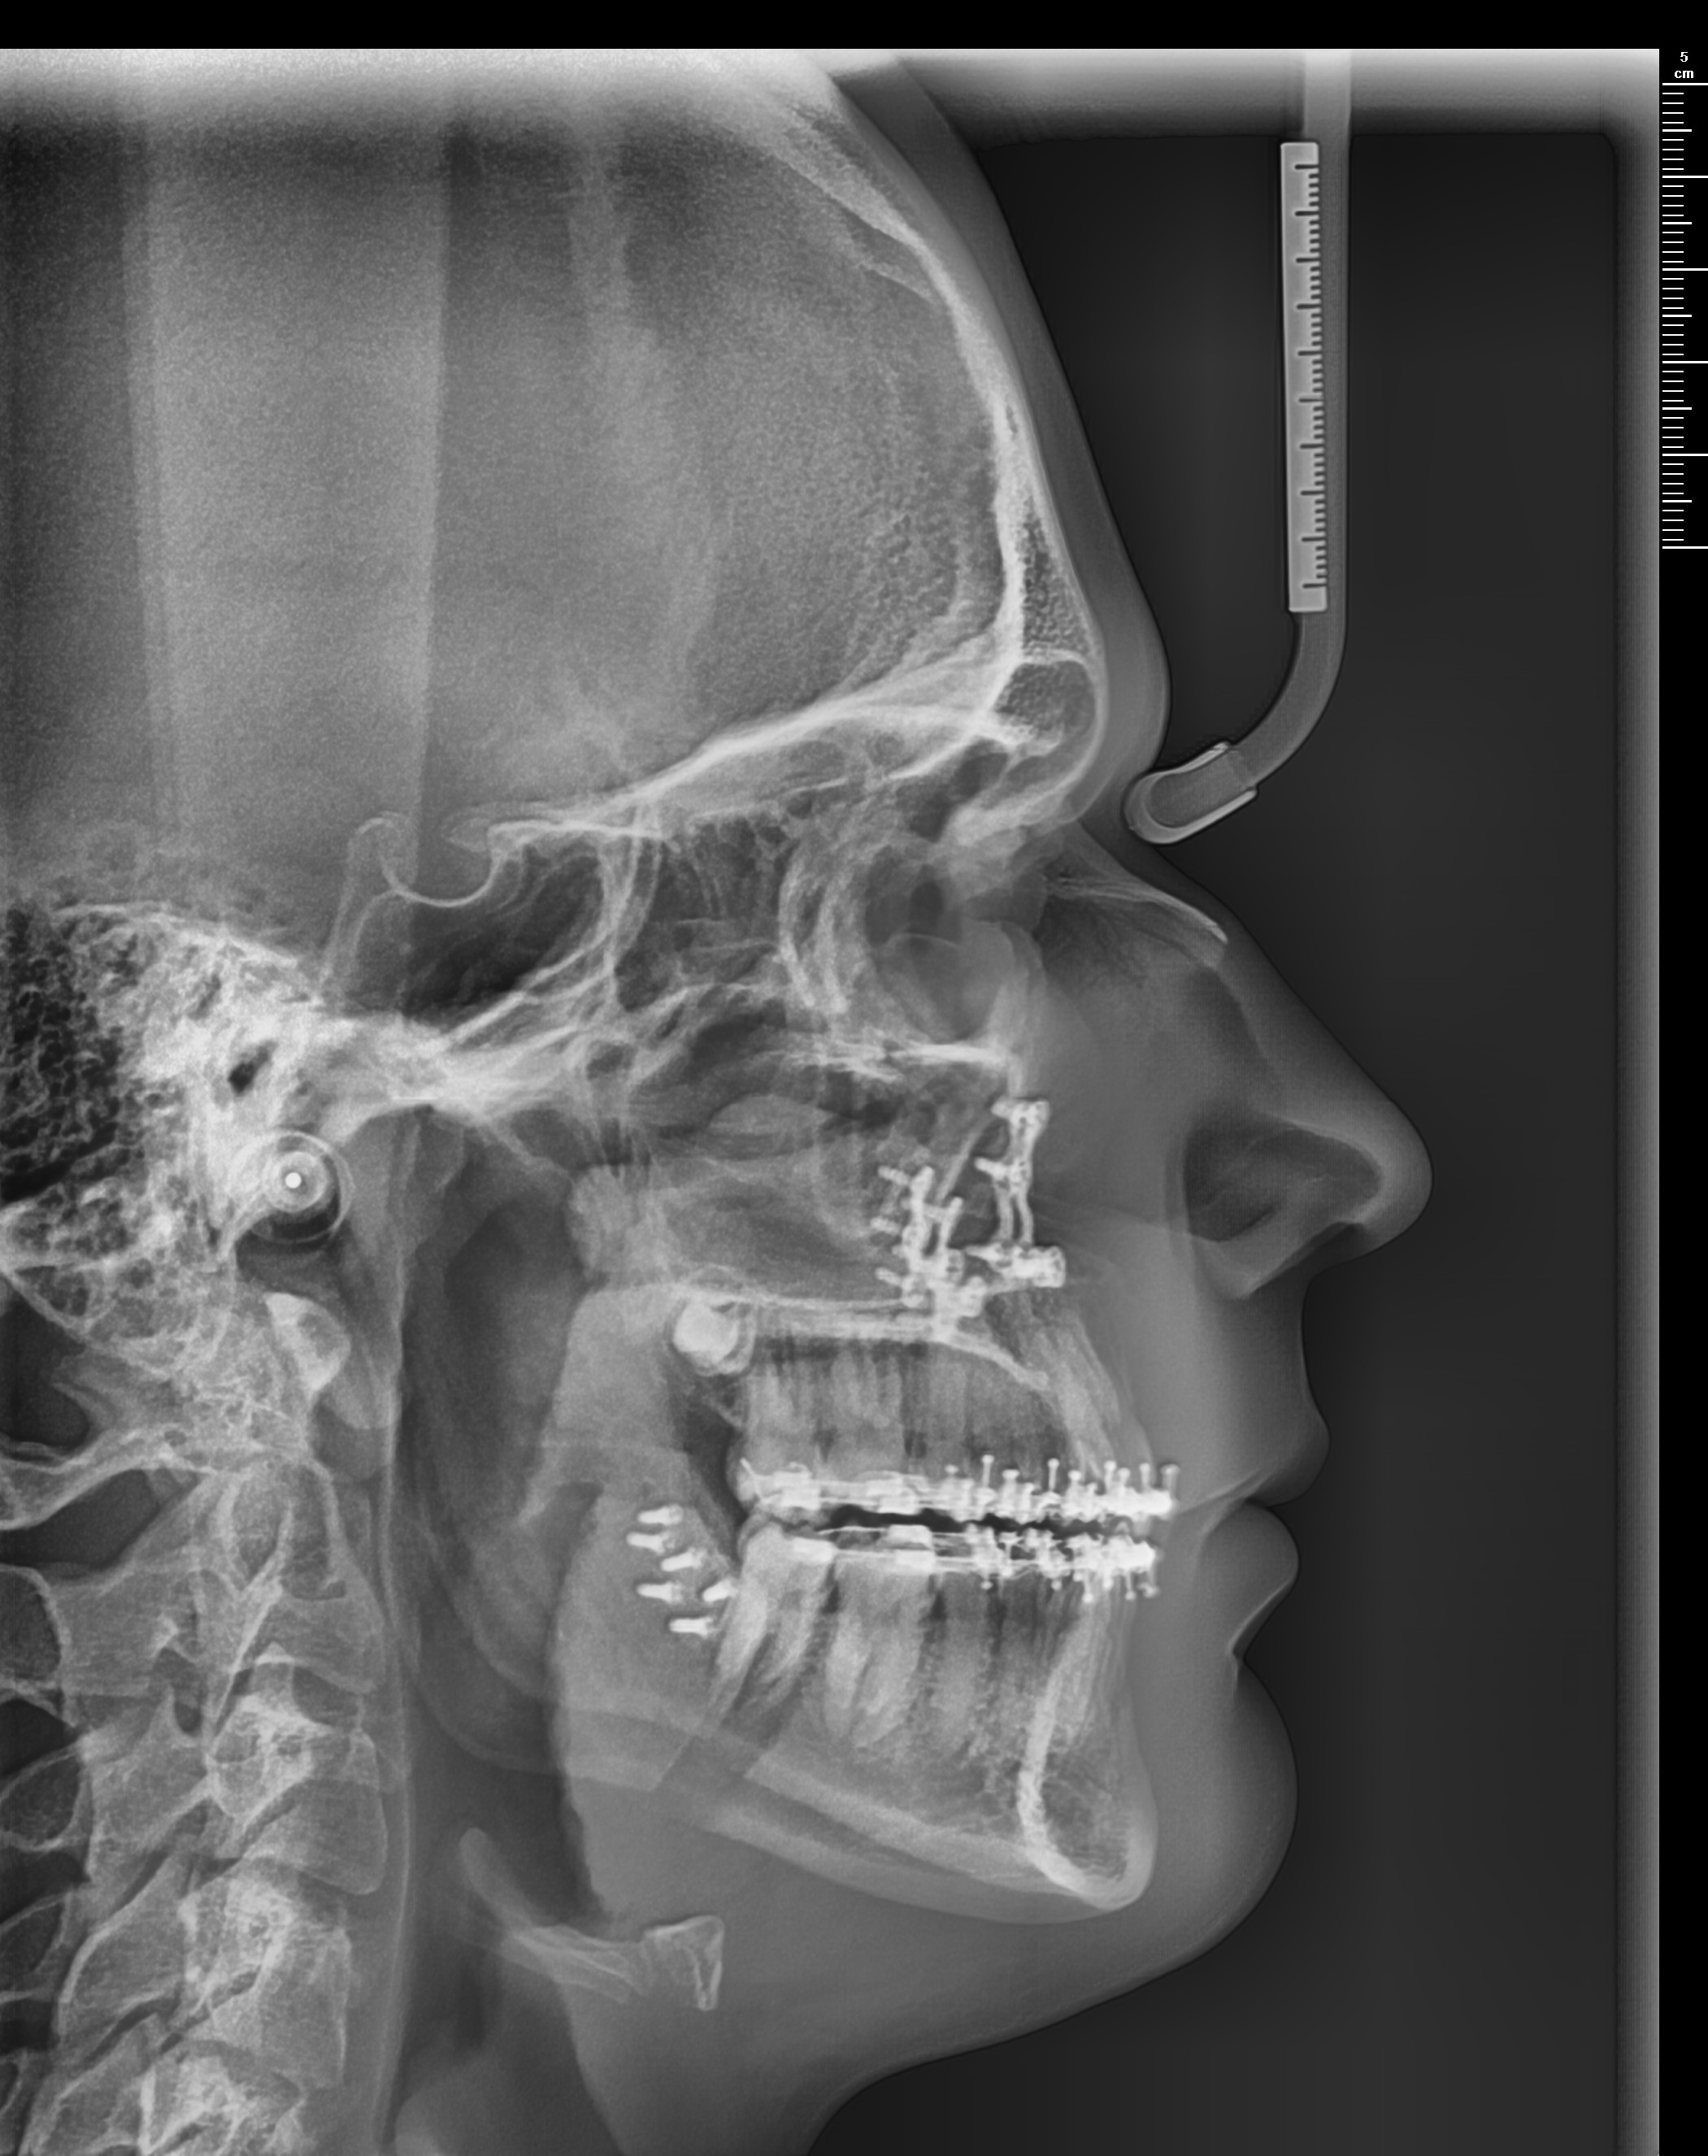

Got a Bimax late september via insurance. These were the movements planned.

LEFORT 1: 2MM ADVANCEMENT

BSSO: 8MM ADVANCEMENT

2° CCW ROTATION

POST BIMAX

My question is: Did I get underadvanced? I'm aware swelling takes longer to go away but atm I still feel like my jaw is recessed.